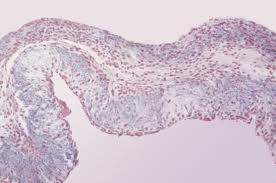

Битторфа—Тушинского симптом. Признак эндотелиоза (например, при затяжном септическом эндокардите): повышенное число гистиоцитов в крови, взятой из мочки уха после легкого ее массажа. Вальдмана симптом (баночная проба). Признак эндотелиоза (затяжного септического эндокардита, ревматизма). Способ исследования: ставится обычная медицинская банка под левой ключицей на 20 мин, потом берется мазок крови из кровоподтека после банки (мазок I) и […]